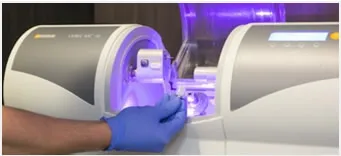

Milling Machine 48 Hours Crowns & Bridges

Ciudadela Dental Implants has the Highest State of the Art Facility for Dental Implants in Puerto Rico